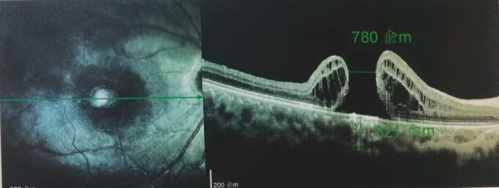

由于自身患有頸椎病,每次術(shù)后長(cháng)期的趴睡都讓他痛苦不堪。為了尋求更好的治療,吳爺爺來(lái)到廈門(mén)大學(xué)附屬廈門(mén)眼科中心,找到了眼外傷及眼底病2科的李海波博士后。此時(shí),吳爺爺右眼的黃斑裂孔已經(jīng)持續擴大到780μm,演變?yōu)殡y治性的大裂孔。

最讓吳爺爺難以置信的是:術(shù)后只需保持平躺24小時(shí)!第二天復查時(shí),眼底鏡及OCT檢查清晰顯示——那個(gè)折磨了他大半年的大裂孔,竟然閉合了!且吳爺爺的右眼視力有了明顯的改善,術(shù)后3天已經(jīng)可以看到 0.15。